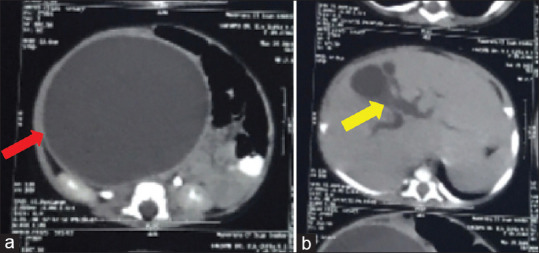

The cystic dilatation of the common bile duct (CBD) is a rare pathology in an infant. It is the second-most common surgical cause of cholestatic jaundice in infants after biliary atresia. A 4-month-old female child was admitted to our department with complaints of abdominal distension. The physical examination revealed the presence of a huge palpable mass involving the right hypochondrium up to the right iliac fossa and umbilical region. Ultrasound abdomen revealed a large intra-abdominal cyst but unable to comment on the organ of origin of the cyst due to its huge size. Multidetector computed tomography of the abdomen was suggestive of possible origin of the cyst from CBD extending from porta hepatis to pelvis. At laparotomy, there was a huge choledochal cyst extending from porta hepatis to pelvis. The choledochal cyst was excised, followed by Roux-en-Y hepaticojejunostomy.